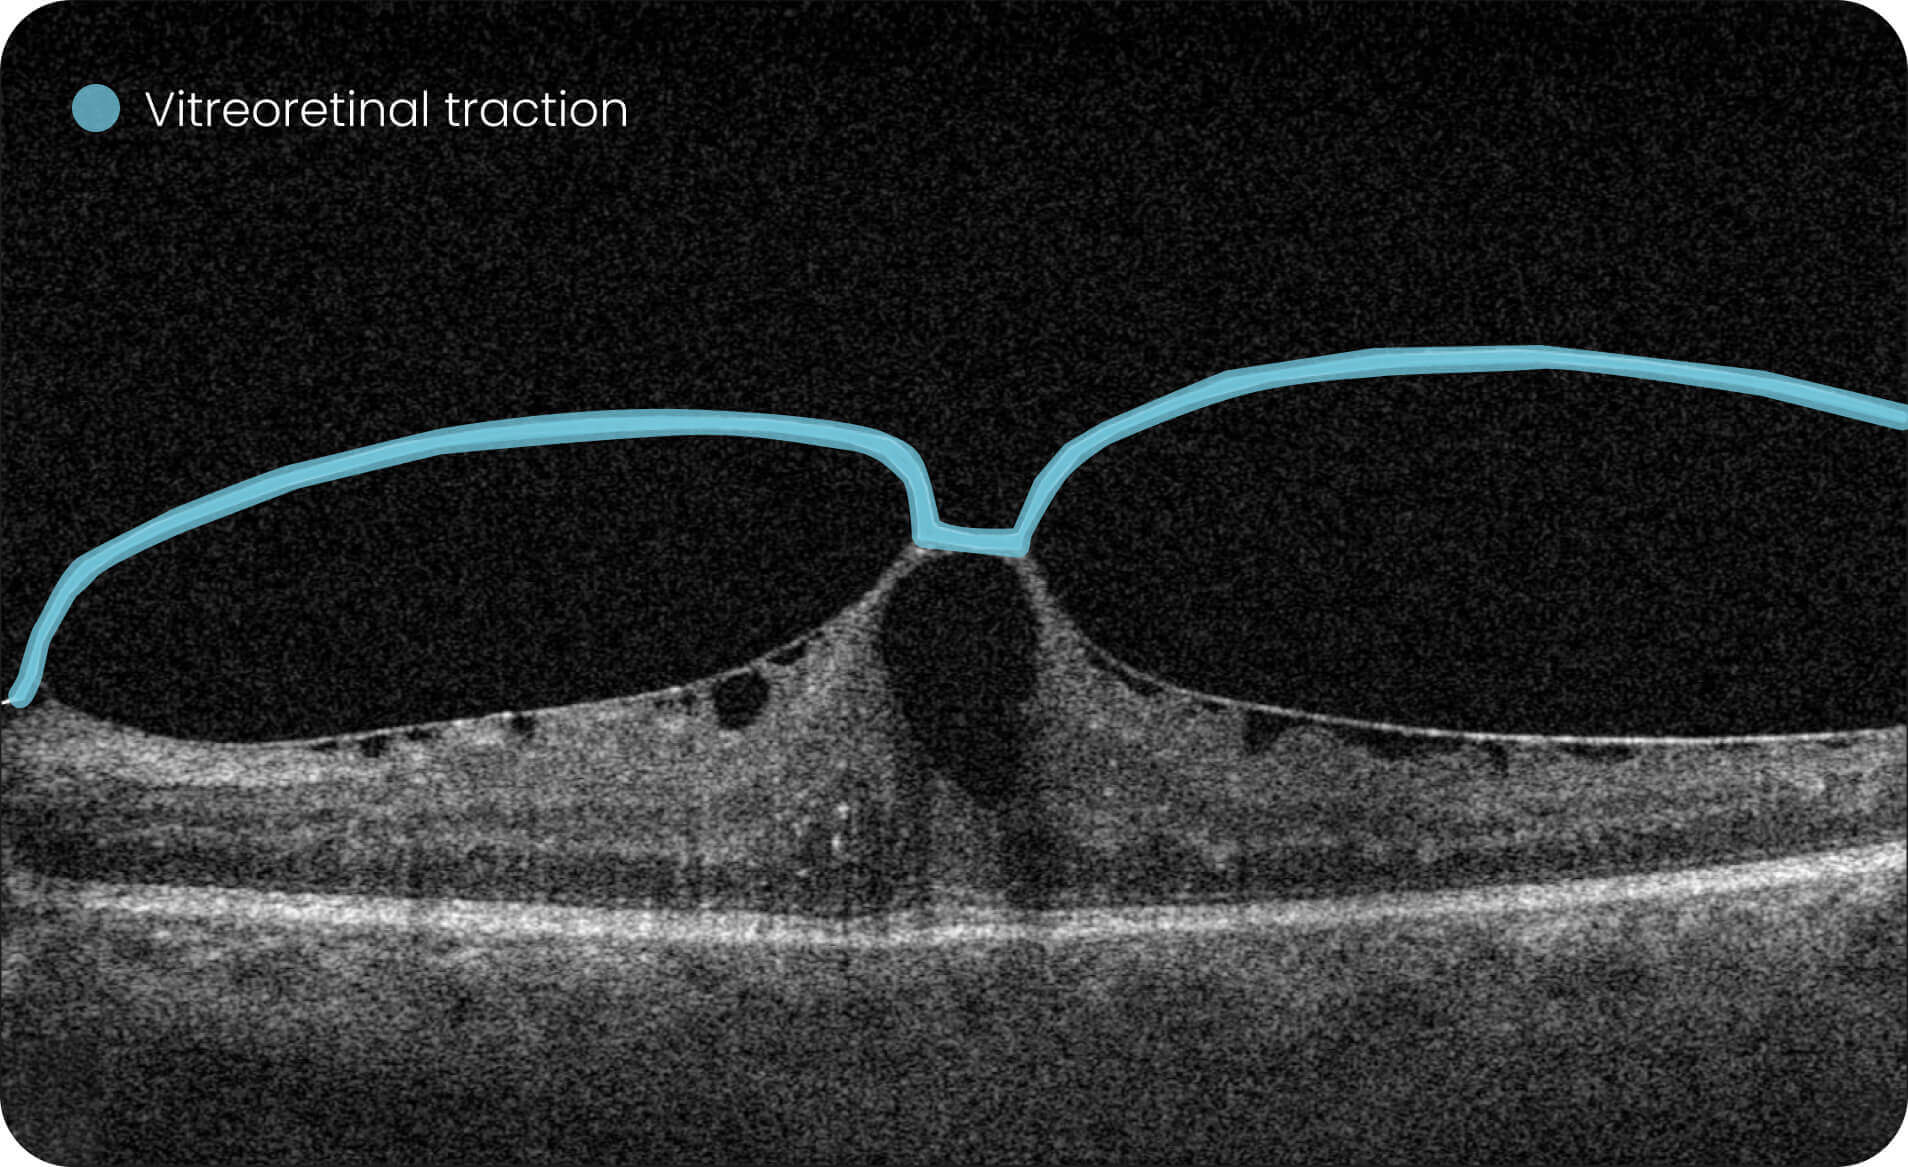

The AI wet age-related macular degeneration in USA platform supports visualization and quantitative, image-derived characterization of OCT imaging features commonly associated with Wet AMD, presented with spatial context on ETDRS-style grids and B-scan views.

Altris AI Models  Research Use Only (RUO). Not for use in diagnostic procedures. These tools enable quantitative, algorithmic exploration of OCT data for research and analytical purposes, including the study of over 40 retinal biomarkers and more than 30 retinal conditions, such as Wet AMD.

• Annotate and explore OCT images for research purposes.

• Quantitative measurements of retinal biomarkers, fluid volume, and drusen count for investigational/analytical purposes only.

Investigation of 40+ retinal biomarkers and 30+ retinal conditions, such as Wet AMD